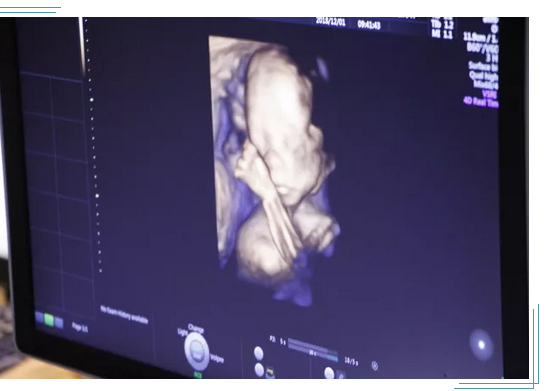

为了每个家庭都能拥有一个健康宝宝,大连美琳达妇儿医院引进新一代GE-E10四维彩超。GE-E10四维彩超能够表面成像,若胎儿有唇腭裂、四肢发育畸形、脑膜膨出、脊柱裂、腹壁裂等先天畸形,都能更清晰地查出来,也有利于医生做出判断。